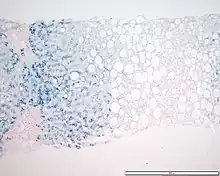

In histology, histopathology, and clinical pathology, Perls Prussian blue is a commonly used method to detect the presence of iron in tissue or cell samples.[1]: 235 [2][3][4] Perls Prussian Blue derives its name from the German pathologist Max Perls (1843–1881), who described the technique in 1867.[2] The method does not involve the application of a dye, but rather causes the pigment Prussian blue to form directly within the tissue.[5] The method stains mostly iron in the ferric state which includes ferritin and hemosiderin, rather than iron in the ferrous state.[6]

Perls's method is used to indicate "non-heme" iron in tissues such as ferritin and hemosiderin,[6] the procedure does not stain iron that is bound to porphyrin forming heme such as hemoglobin and myoglobin.[2] The stain is an important histochemical stain used to demonstrate the distribution and amount of iron deposits in liver tissue, often in the form of a biopsy.[6][7] Perls's procedure may be used to identify excess iron deposits such as hemosiderin deposits (hemosiderosis) and in conditions such as hereditary hemochromatosis.[8] Perls Prussian blue is commonly used on bone marrow aspirates to indicate levels of iron storage[4] and may provide reliable evidence of iron deficiency.[7]

Perls did not publish a detailed procedure other than indicating a dilute potassium ferrocyanide solution was applied to the tissue followed by hydrochloric acid.[2] Ferric iron deposits in tissue (present mostly as ferric iron within the storage protein ferritin) then react with the soluble ferrocyanide in the stain to form the insoluble Prussian blue pigment (a complex hydrated ferric ferrocyanide substance). These deposits are then visualizable microscopically as blue or purple deposits.[9]

Many methods of performing Perls Prussian blue stain for iron have been published, [2] Drury and Wallington (1980) give a protocol that uses a mixture of 1 part 2% hydrochloric acid and 1 part 2% potassium ferrocyanide that is applied to the section for 20–30 minutes followed by a rinse in distilled water and application of a counterstain such as eosin, safranin or neutral red.[5]